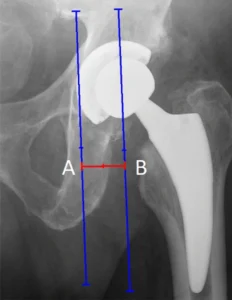

Lunghezza dell’arto e offset femorale

La radiografia post-operatoria consente una valutazione preliminare della lunghezza dell’arto operato e del ripristino dell’offset femorale. Alterazioni significative di questi parametri possono avere ripercussioni funzionali importanti, influenzando la biomeccanica dell’anca, la deambulazione e la soddisfazione del paziente.

È importante sottolineare che la valutazione radiografica deve essere sempre integrata con l’esame clinico, poiché piccole differenze radiografiche possono non essere clinicamente rilevanti e viceversa.